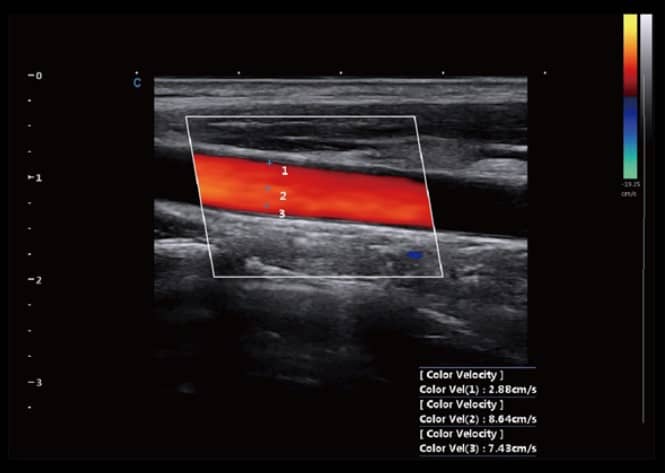

- Hình Ảnh Toàn Cảnh Màu: Phóng to vùng quét và cung cấp nhiều thông tin về màu sắc, đặc biệt hữu ích cho việc phân tích mạch máu lớn.

- SonoColor và SonoContrast: Cung cấp phân tích dòng định lượng và độ nhạy cao hơn, thích ứng với mọi loại đầu dò.